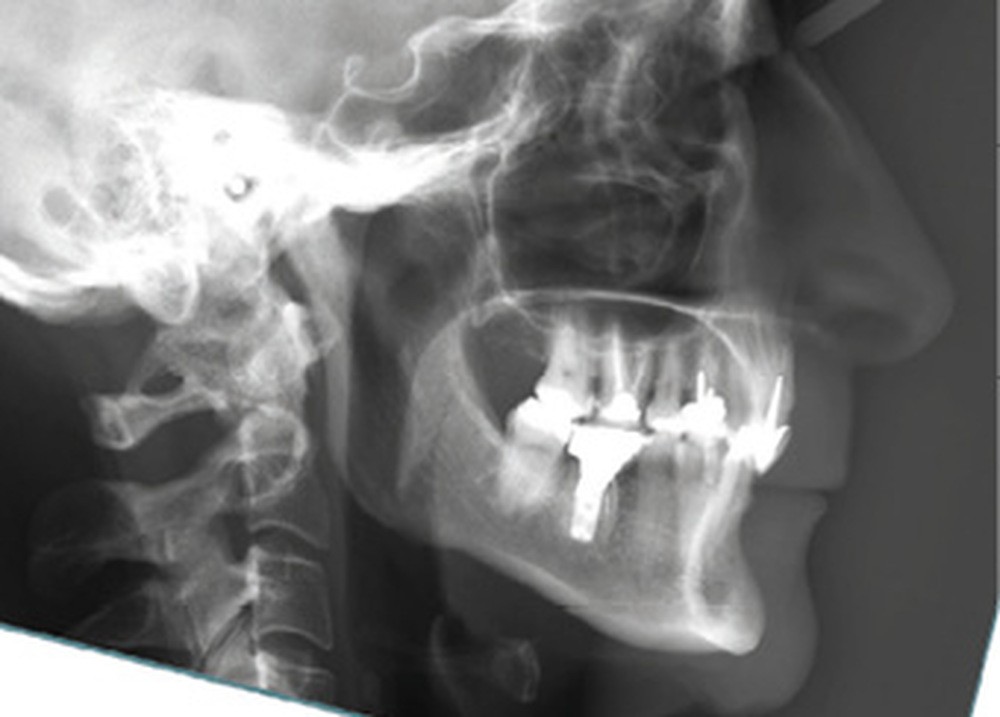

Examens complémentaires (fig. 3)

La téléradiographie de profil et l’analyse céphalométrique montrent une classe I squelettique tendance classe II dans un contexte d’hypodivergence avec diminution de l’étage masticatoire. L’axe de l’incisive mandibulaire est en normoposition, alors que l’incisive maxillaire présente une rétroalvéolie importante.

La supraclusion antérieure est d’origine mandibulaire en lien avec une courbe de Spee marquée quantifiée à 3 mm. L’orthopantomogramme confirme la présence d’un implant en 36.